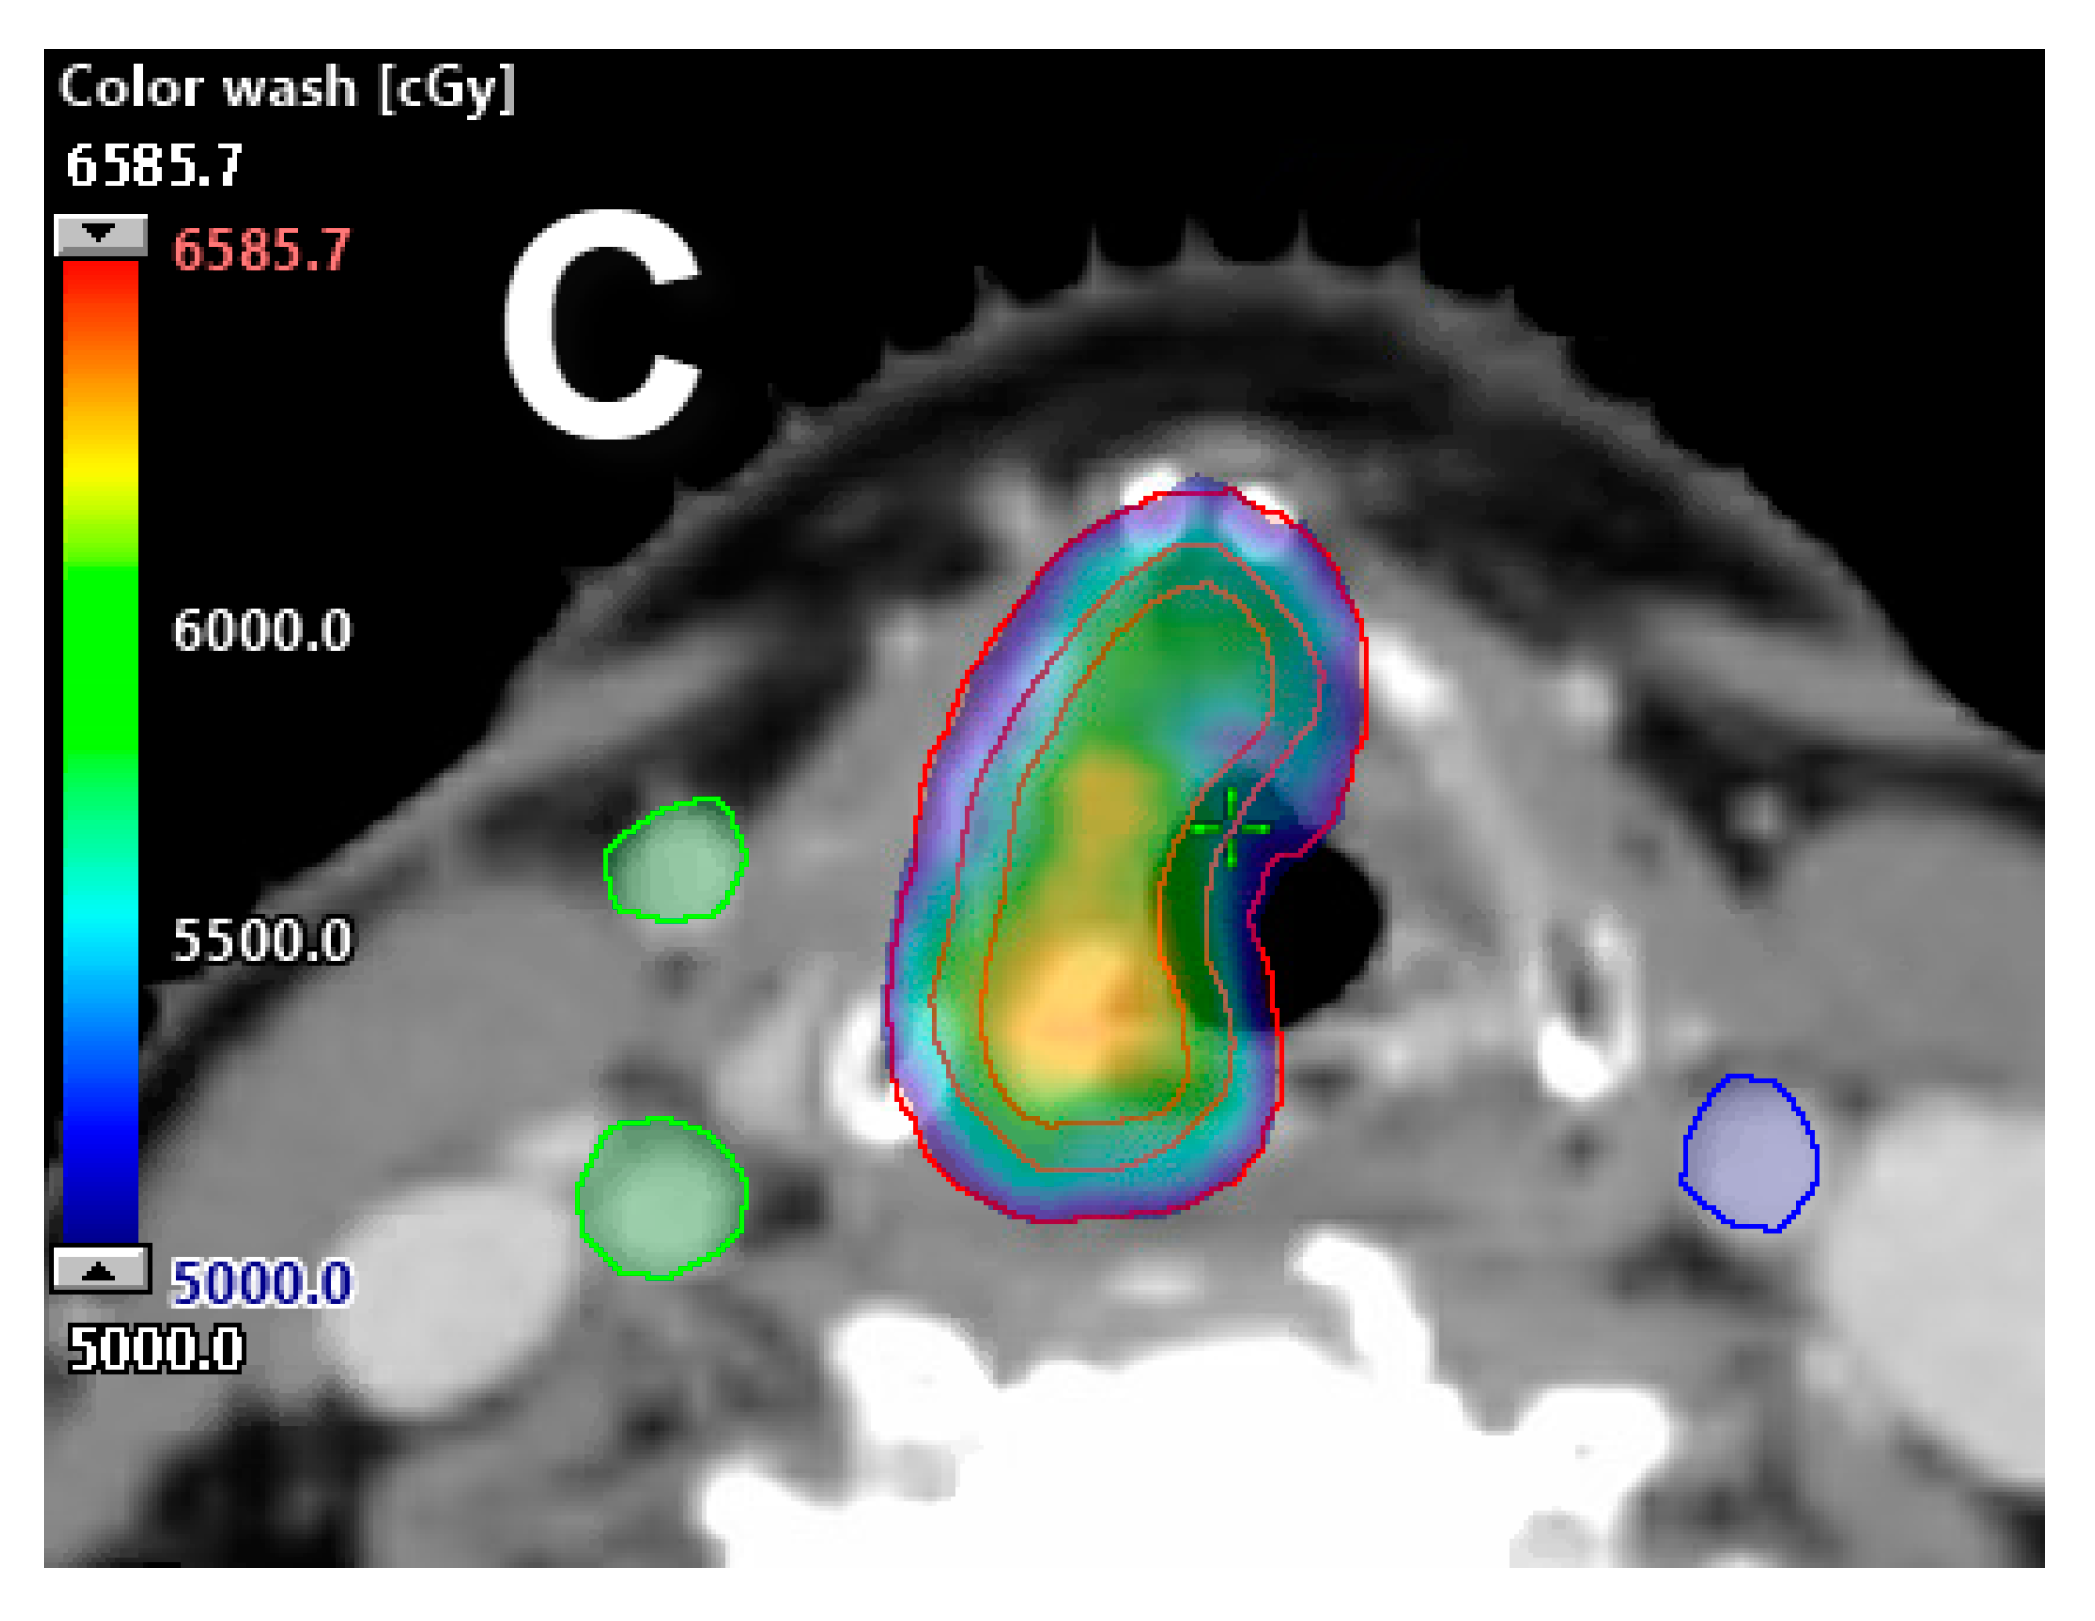

- Moreno, A.C.; Frank, S.J.; Garden, A.S.; Rosenthal, D.I.; Fuller, C.D.; Gunn, G.B.; Reddy, J.P.; Morrison, W.H.; Williamson, T.D.; Holliday, E.B.; et al. Intensity modulated proton therapy (IMPT)—The future of IMRT for head and neck cancer. Oral Oncol. 2019, 88, 66–74. [Google Scholar] [CrossRef]

- Anand, A.; Bues, M.; Gamez, M.E.; Stefan, C.; Patel, S.H. Individual field simultaneous optimization (IFSO) in spot scanning proton therapy of head and neck cancers. Med. Dosim. 2019, 44, 375–378. [Google Scholar] [CrossRef]